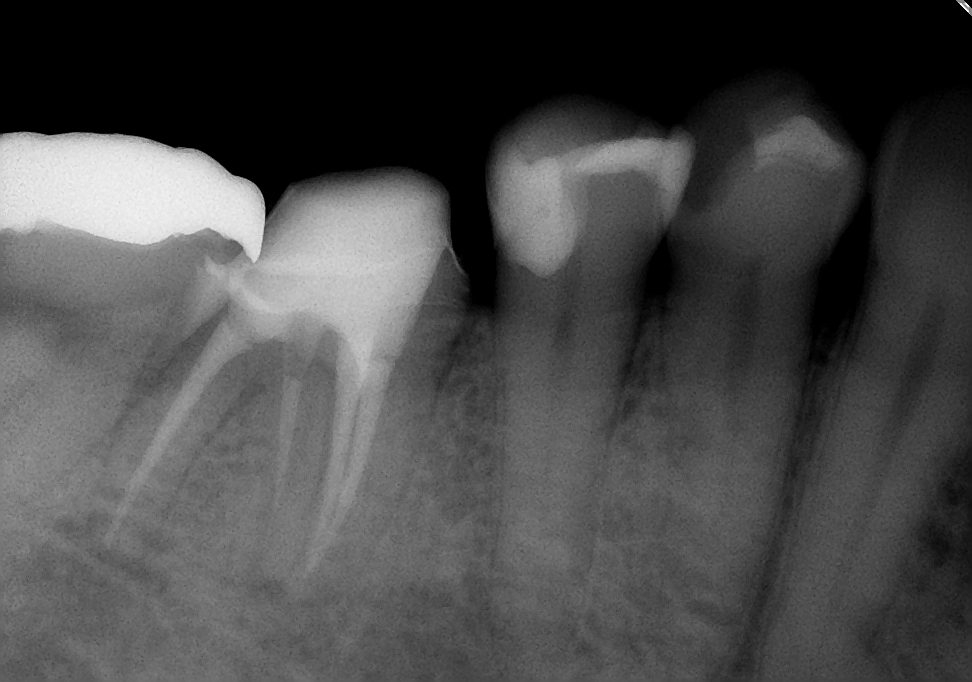

↑7ヵ月後

初診時に溶けていた骨もだいぶ再生されてきました。7ヶ月間症状も特になく、気にすることなく左右バランスよく咬めるとの事。ということで、主治医の先生でかぶせ物を入れてもらうことにしました。まずは一安心(^o^)